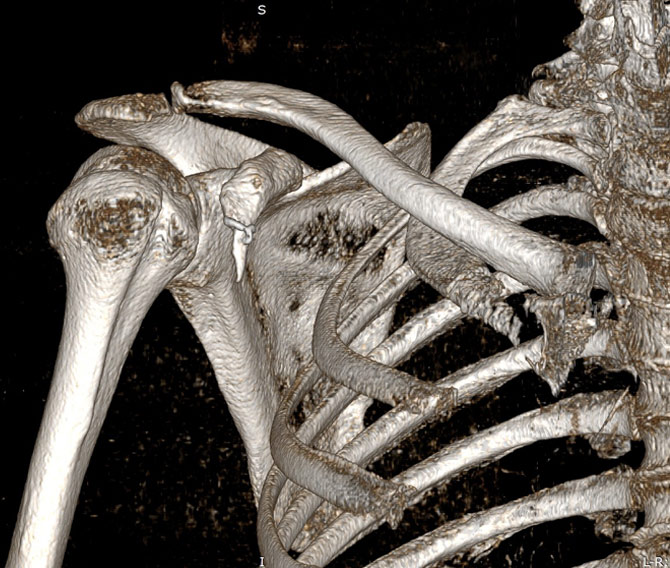

Reconstrucții tridimensionale

În final, pentru a veni în ajutorul medicului radiolog sau ortoped, examinarea trebuie să se încheie cu o reconstrucție 3D, cel mai frecvent de tip VRT (volume rendering), care să permită rotirea volumului de examinat în orice direcție și aprecierea suprafeței osoase și a traiectelor de fractura/ fragmentelor osoase din focar.

Image

Reconstrucție tridimensională a oaselor din articulația umărului (VRT)

Aspect de rotație în jurul axului a unei reconstrucții 3D